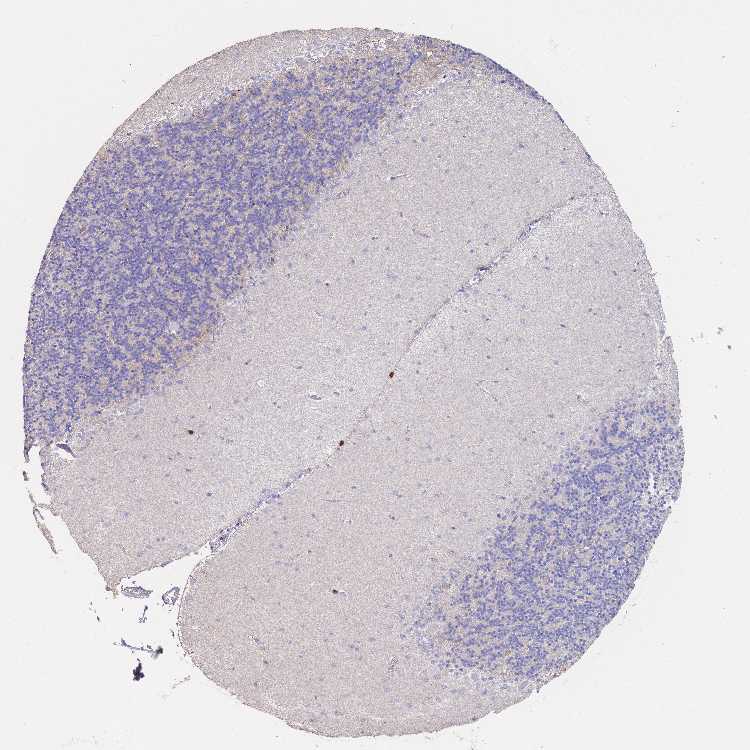

CEREBELLUM - Antibody stainingi

Antibody staining in the annotated cell types in the current human tissue is reported as not detected, low, medium, or high, based on conventional immunohistochemistry profiling in selected tissues. This score is based on the combination of the staining intensity and fraction of stained cells.

Each image is clickable and will lead to virtual microscopy that enables deeper exploration of all samples and also displays staining intensity scores, fraction scores and subcellular localization as well as patient and tissue information for each sample.

Antibody HPA048515

Purkinje cells Not detected

Cells in granular layer Not detected

Cells in molecular layer Not detected